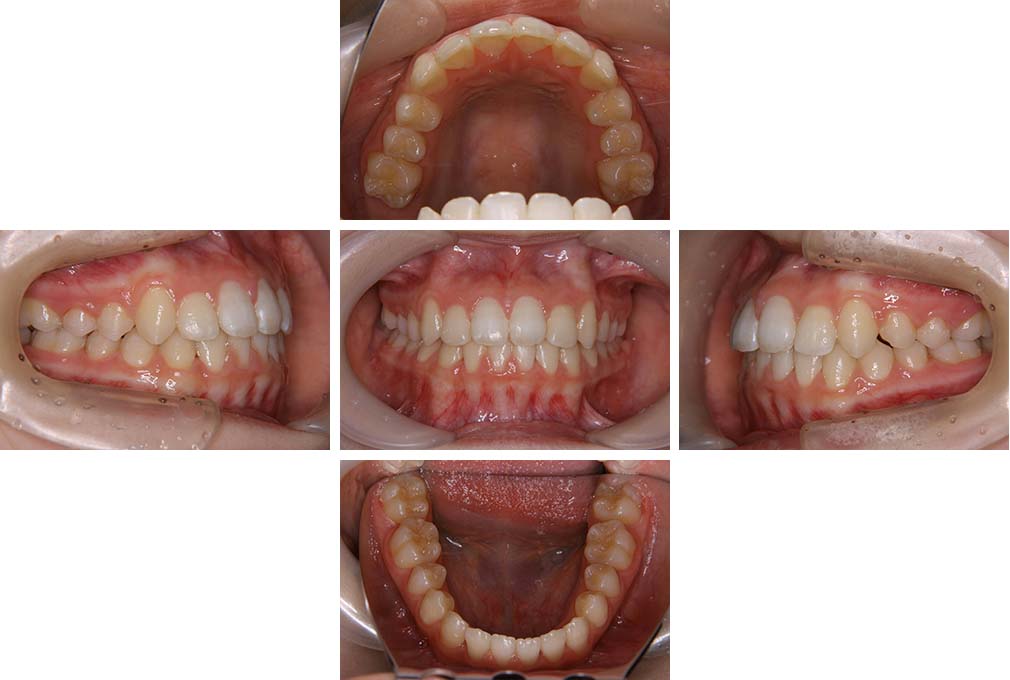

CASE:02

下顎前歯部叢生、小臼歯4歯先天欠損

初診時年齢 14歳3か月

性別 女性

治療費の目安 70万円(治療開始時)

上顎左右側小臼歯3歯、下顎左側第二小臼歯の先天欠損と下顎前歯の叢生を主訴として近隣一般歯科から紹介来院した。

上顎左側第一、第二小臼歯、右側第一小臼歯、下顎左側第二小臼歯が先天欠損であったが、左上第二乳臼歯の根の吸収がほぼ無いことから、これを残すこととして、下顎左側乳臼歯と、右側第二小臼歯を抜歯していただきマルチブラケット装置を使用して動的治療を行った。矯正用ゴムなどの協力状態も良く2年0カ月(調整来院19回)で装置を撤去し保定へ移行した。動的治療終了13年2カ月での来院時には下顎左右側智歯が萌出していたが、垂直的に萌出していたため抜歯は行っていない。

治療前

14歳3か月

治療後

動的治療期間2年0カ月

16歳7か月

13年経過

動的治療終了後13年2カ月

30歳0か月